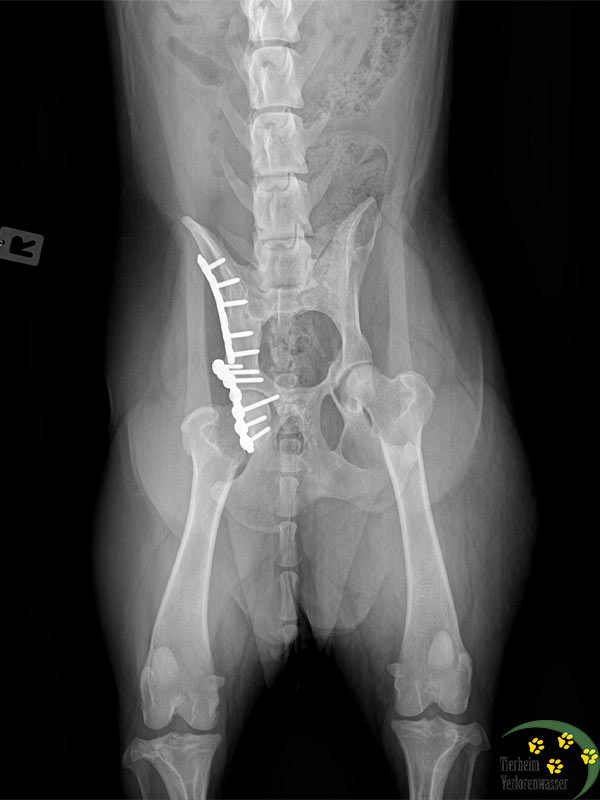

Beide hatten arge Gelenkprobleme. Deshalb fuhren wir zu einem spezialisierten Chirurgen nach Berlin. Bei Frieda musste der Tierarzt in einer komplizierten Operation die Platten entfernen, die früher einmal bei ihr eingesetzt worden waren. Es hatten sich Schrauben gelockert. Frieda konnte nicht mehr richtig laufen und litt große Schmerzen.